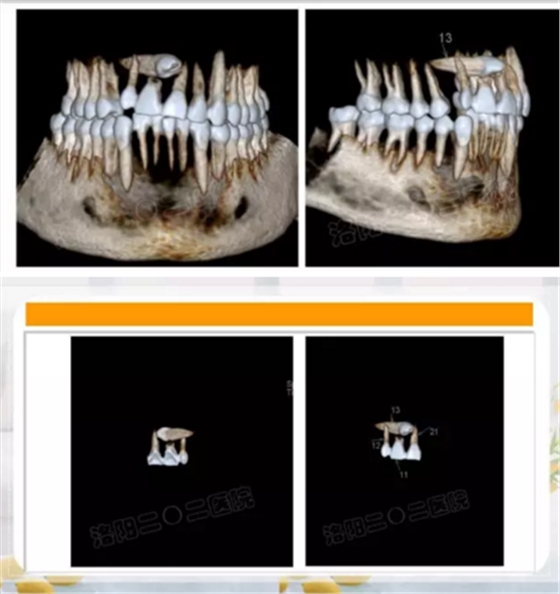

奇異牙齒進(jìn)鼻腔

倒立